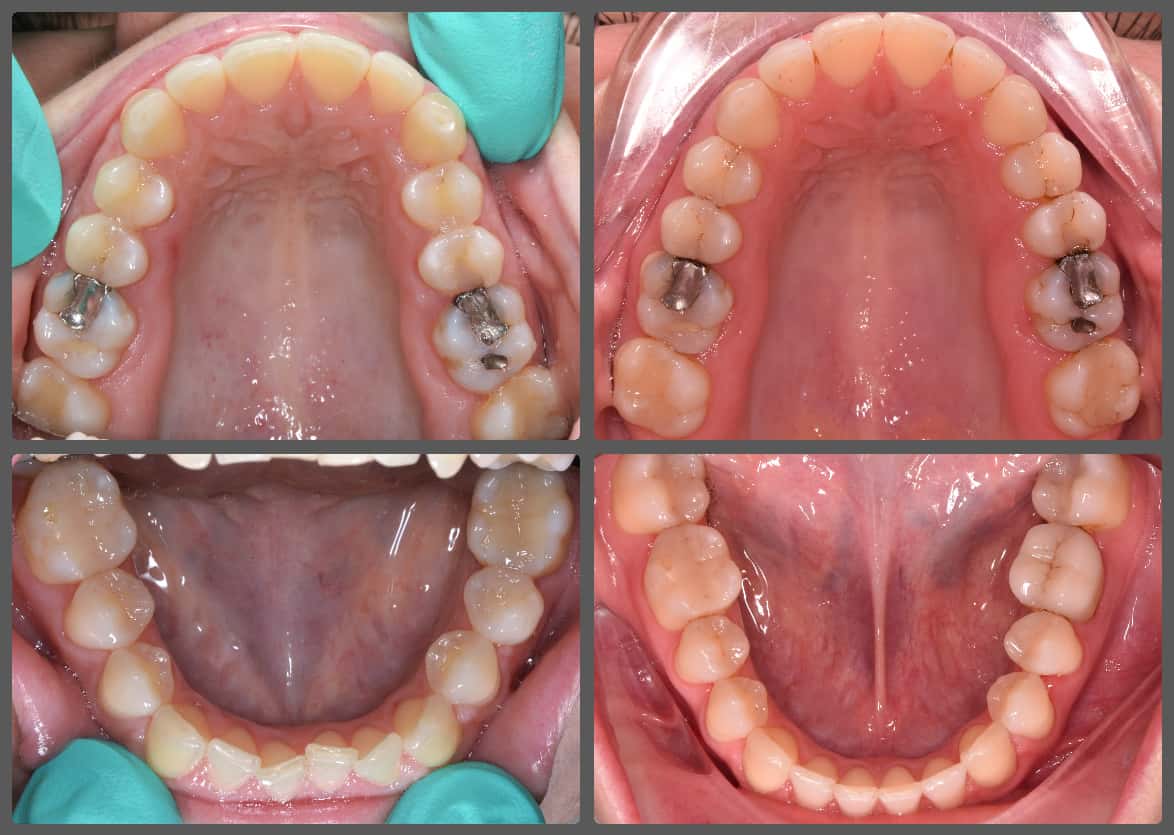

Extrém súlyos alsó-felső torlódása miatt jött hozzám fogszabályozási konzultációra Viki. A korábbi szakvélemények mindegyike foghúzással járt volna. Súlyosan eltolódott alsó-felső középvonalat, súlyos alsó-felső torlódást, mélyharapás, fogívszűkületet és a nyelv felé dőlő fogíveket diagnosztizáltam. Viki harapási és anatómiai adottságai miatt úgy ítéltem meg, hogy a kezelését foghúzás nélkül is végig tudjuk vinni. H4 önligírozó fogszabályzó készüléket ragasztottunk Vikinek, és a torlódott területeken tolórugóval csináltunk helyet a fogívből kiszorított fogaknak. A harapás harmonizálást és a mélyharapás korrekcióját intermaxilláris gumihúzással, valamint harapásemelőkkel végeztük. A teljes kezelés 26 hónapig tartott, melynek végére egy igazán gyönyörű, telt mosolyt sikerült Viki arcára varázsolni, mindemelett a szinte tökéletes oldalsó fogilleszkedést is megtartottuk, tovább javítottuk. Az ilyen látványos változások, páciens átalakulások miatt szeretem a legjobban a munkám!